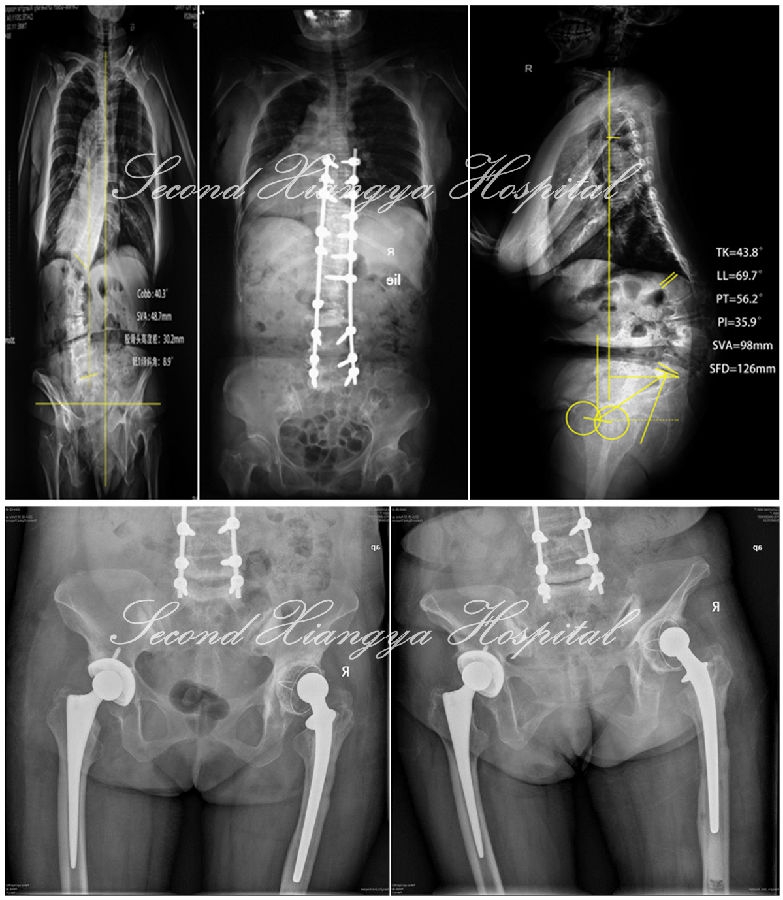

- 刘某某,女,63岁,脊柱后凸并腰痛20年

- 2年前加重并出现双侧臀部疼痛,沿双侧大腿外侧放射至膝关节,右侧为甚,并间歇性跛行及双下肢麻木感。

- 查体:脊柱S型侧弯,腰椎后凸,双下肢感觉减退,右髋关节活动明显受限,右侧直腿抬高及加强试验(+),双侧4字征(+),双侧托马斯征(+)。

- 腰椎退变性侧凸合并髋关节OA

- 手术:腰椎减压、长节段矫形融合术,2年后右侧THA,随后1年再行左侧THA,右髋随访2年松动进行翻修